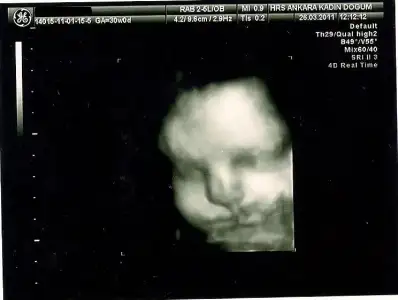

28.haftada bu kadarsa 4 kilo doğar maşallah